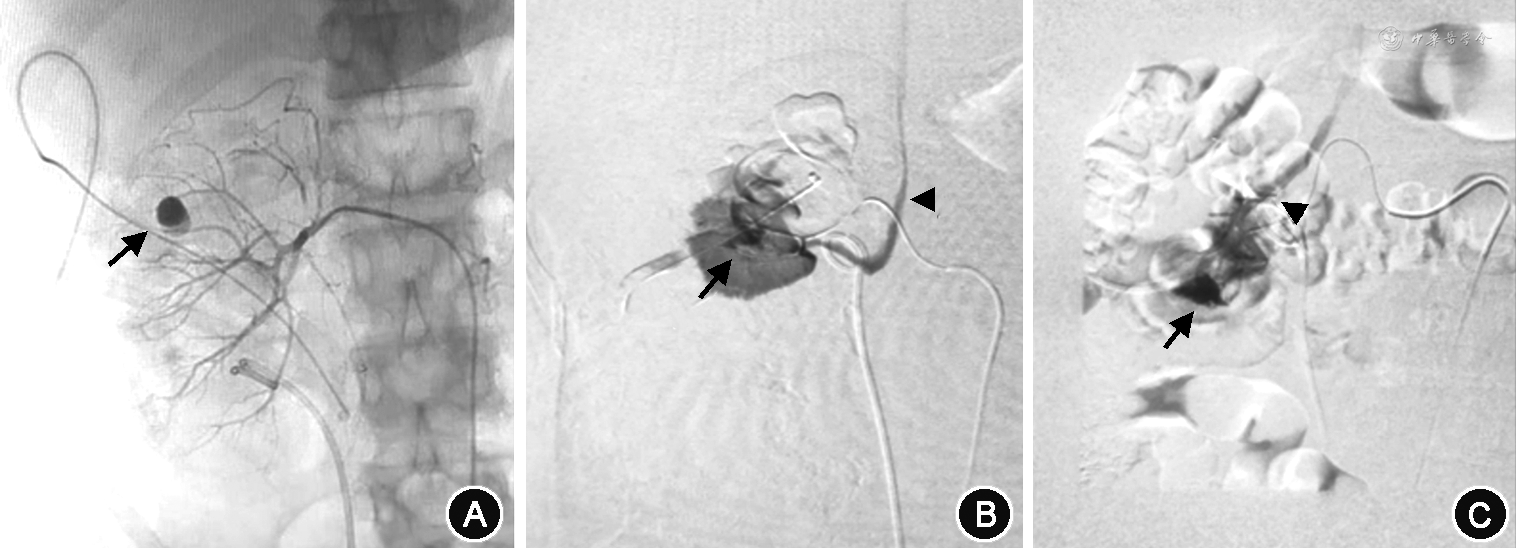

2. 诊断与治疗方法:27例患者均在保守治疗无效后急诊局麻下经皮股动脉穿刺插管至患肾动脉,行选择性肾动脉造影,初次造影结果为阴性,未发现出血部位。再保守治疗1~3 d无效后,经反复肾动脉造影,最后均发现血管损伤病变。其中15例假性动脉瘤(图1A),4例动静脉瘘(图1B),8例假性动脉瘤合并动静脉瘘(图1C)。23例行2次、4例行3次肾动脉造影。分析原因,其中一味追求选择性肾动脉造影,遗漏副肾动脉供血所致出血5例12次(图2、3);两处以上出血,只处理一处出血3例6次;初次未发现出血病变,第二次才发现者17例36次;选择栓塞物不当2例4次。诊断明确后同时行超选择栓塞术,栓塞当时即复查肾动脉造影,27例显示病变完全栓塞,出血点消失,术后患者严重血尿症状立即得到改善,1周内肉眼血尿及腰部不适症状全部消失,尿色转清,血红蛋白持续稳定,拔出肾造瘘管后患者出院;其中5例出现栓塞后综合征,表现为低热、腰部胀痛不适等症状,给予退热、止痛等对症处理后症状消失。